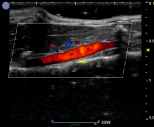

小鼠-腹主动脉彩色血流 小鼠-腹主动脉频谱多普勒 小鼠-左心室短轴 小鼠-心脏彩色血流